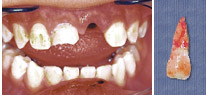

牙冠折斷牙齒移位

意外碰傷牙齒后的處理方法

3.jpg

學(xué)童如因意外碰傷而導(dǎo)致牙齒部份崩裂、移位或者插入牙床,應(yīng)盡快見牙科醫(yī)生,即使牙齒表面沒受傷,也應(yīng)該檢查一下。因?yàn)榕鰝牟糠菘赡茉诒砻婵床坏降奈恢?,例如牙根;而且,乳齒受創(chuàng)可能傷害形成中的恒齒。假如牙齒折斷了,應(yīng)該尋回折斷的部份,一并拿去見牙科醫(yī)生。如果學(xué)童已經(jīng)參加牙科保健,可以到所屬的牙科診所,尋求急癥服務(wù)。

整顆恒齒被碰掉的處理方法

假如整顆恒齒被碰掉,4.jpg

整顆恒齒被碰掉的處理方法應(yīng)該馬上拾回,千萬別觸摸或洗刷牙根部份